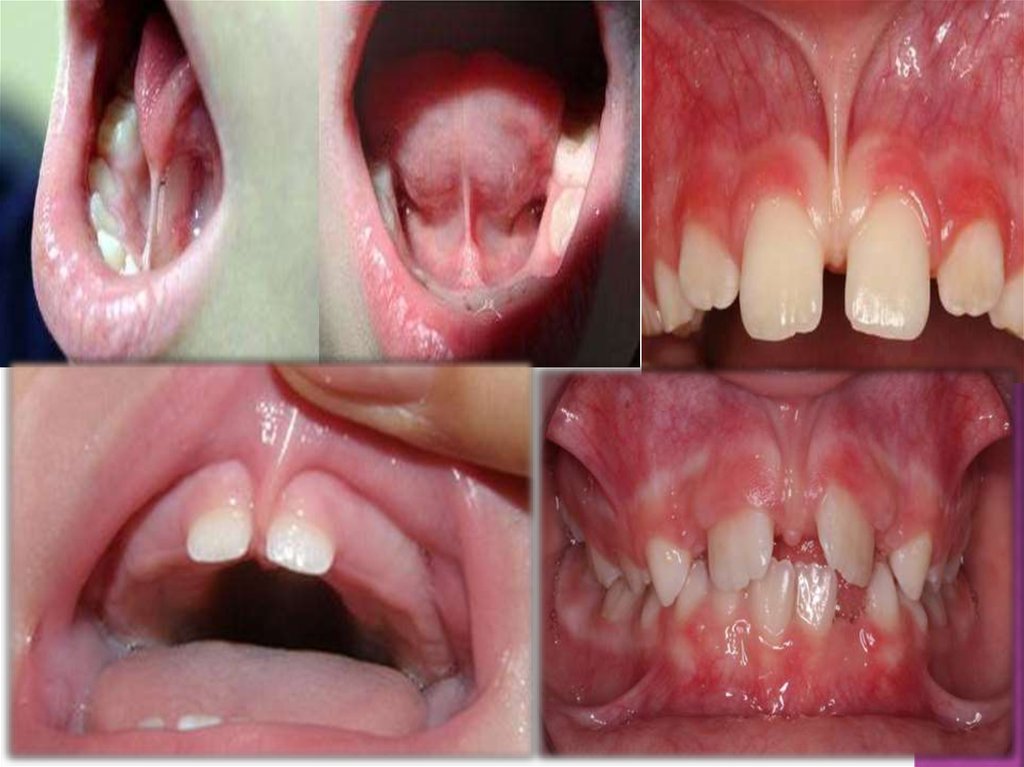

8.

9.

10.

11.

12.

1-

жасында, баланың дұрыс емуыін

қадағалау, себебі осы кезде ауыздың

бұлшық еттерінің жетілуі жүреді және

фротальды бөліктегі сүйек тінінің құрылуы

жүреді.

4-жасында, уақытша тістер арасында трема

көруге болады, осыған байланысты

физиологиялық арақатынасты және тіс

аралық контактілерді, окклюзияның

өзгермеуін қадағалау керек, ерте түскен

тістердін орнын протездермен толтырып,

кариозды тістерді емдеу керек.

13.

6-7

жасында, тістердің тығыз орналасуы

және жұмсақ тіндердің аномальды бекуі

көрінуі мүмкін.